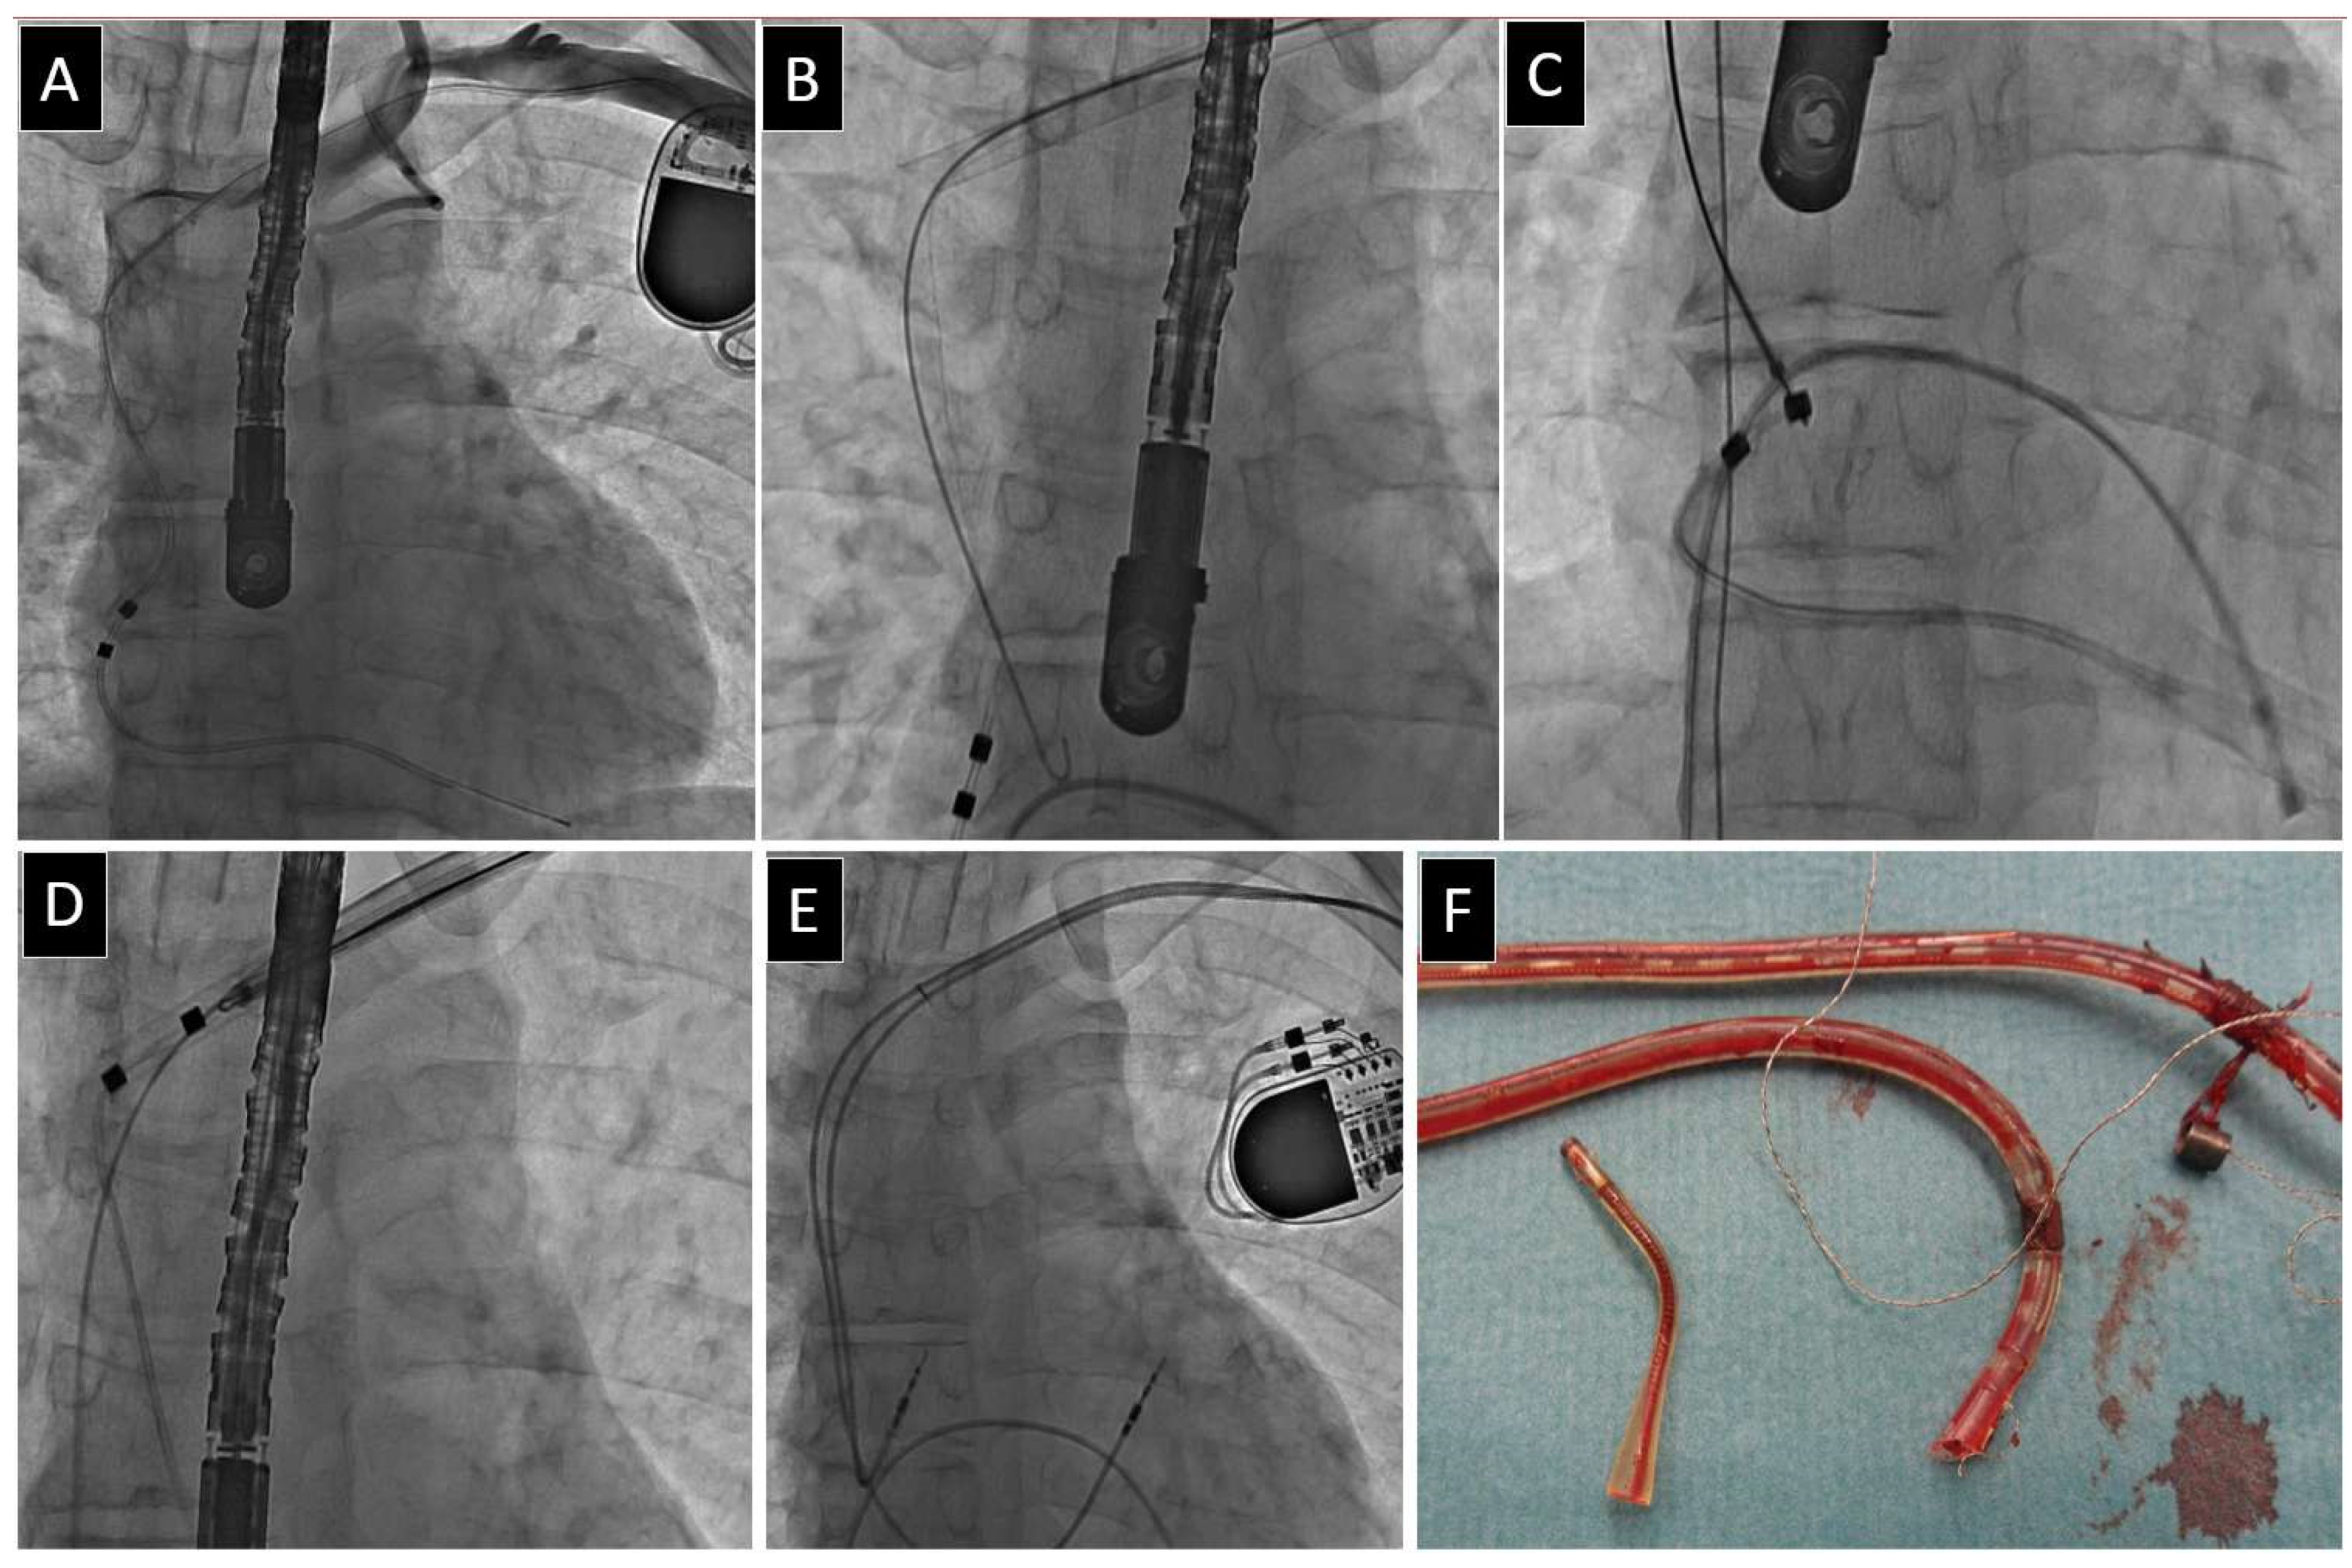

Author Comments on VDD Lead Extraction